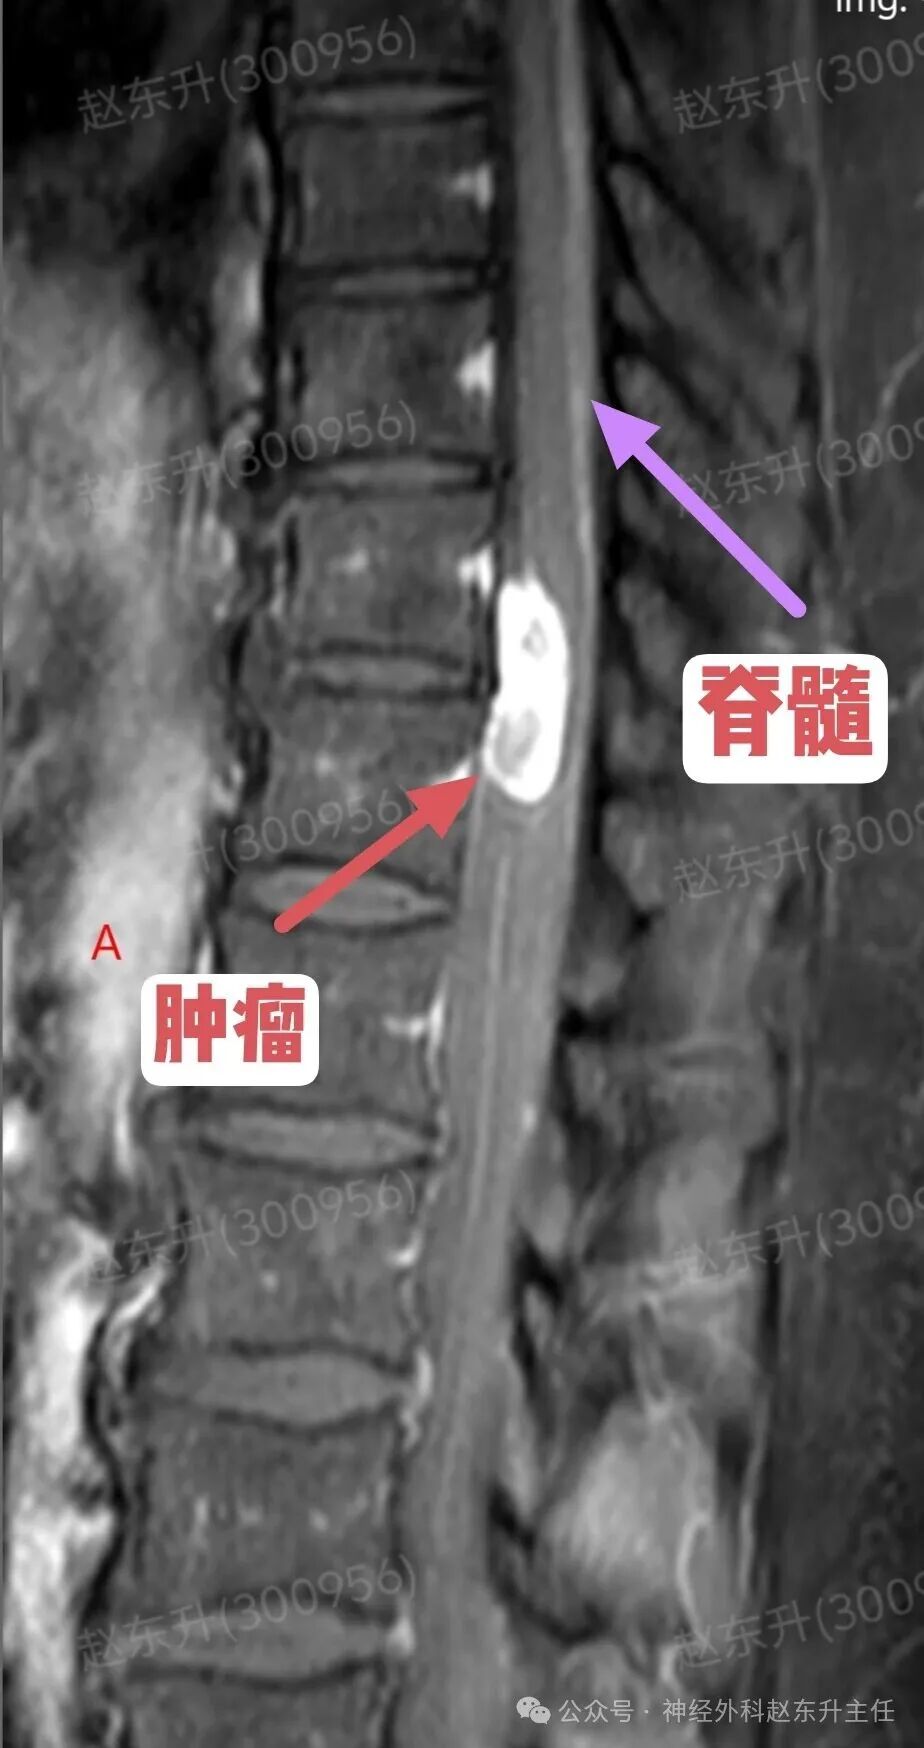

今天介绍一位58岁的男性患者,因为腰背部疼痛半年入院的。他半年前出现腰背部疼痛疼痛评分4-5分半双下肢乏力,但可独立行走。症状尚可忍受,但随后症状逐渐加重,疼痛有7-8分,吃药打针康复理疗。效果不明显,随后到医院查了一个磁共振,发现胸11-12水平椎管内巨大的肿瘤,肿瘤长在脊髓腹侧,外院的医生看了之后认为手术风险太大,不敢做,随后他来到西安市红会医院神经外科找到赵主任。入院后完善术前检查。随后在全麻下进行了肿瘤全切术中使用显微镜并进行术中电生理监测尽最大可能的保护脊髓神经,最终肿瘤予以全切,术后神经没有损伤,下肢可以正常下地活动大小便也正常,患者顺利出院了。

症状早期症状不典型:可能仅表现为相应神经根支配区的疼痛或感觉异常脊髓压迫症状:随着肿瘤增大,从前方直接压迫脊髓,可导致:运动功能障碍为主:由于压迫脊髓前角和皮质脊髓束(运动传导通路),常早期出现肢体无力、僵硬、肌肉萎缩,且可能比感觉障碍更早、更明显。感觉障碍:表现为受压平面以下的痛温觉减退(因压迫脊髓丘脑束)。括约肌功能障碍:大小便困难,出现较晚。不对称症状:由于肿瘤偏于一侧,症状常从一侧开始。影像诊断(MRI是金标准)位置:明确显示肿瘤位于椎管内、脊髓的正前方或前外侧形态与信号:常呈“哑铃形”,部分肿瘤通过椎间孔向椎管外生长。T1加权像呈等或稍低信号,T2加权像呈高信号,增强后显著不均匀强化关键观察点:放射科和外科医生会重点关注肿瘤与脊髓前动脉、椎动脉(颈段)的关系,以及脊髓受压移位的程度。